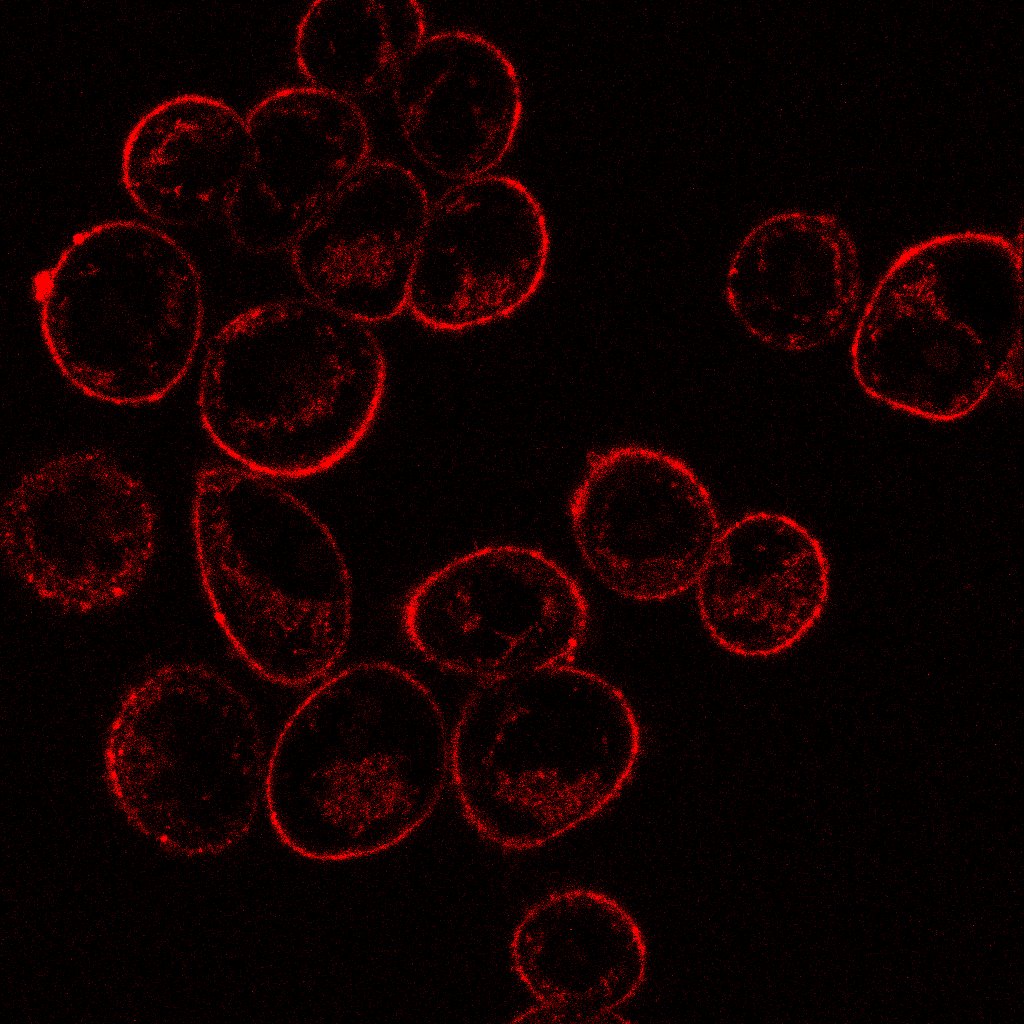

🔬Keep Calm😉 "¿Estrés? Sólo oxidativo..." Autor: Jorge M. Herrero-Lab. M.I. Sánchez Jorge METCAN #ConcursoSEMOC #Microscopía IIBM REMOA-Spanish Network for Advanced Microscopy PPBI-Portuguese Platform of BioImaging